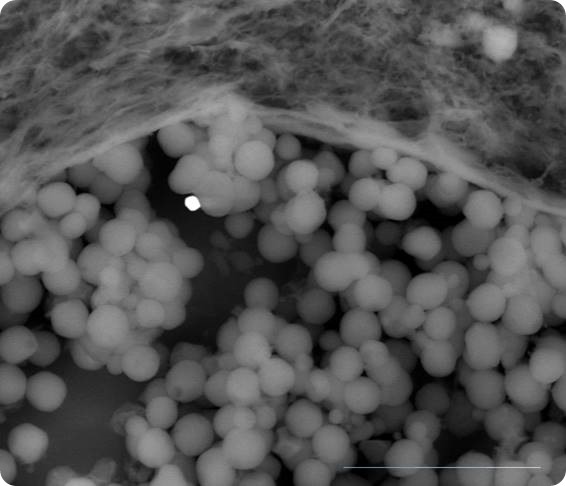

red cells metallic spherule

Blood vessel with red cells and a metallic spherule (Marker 20micron)

really in the first figure it is almost impossible to recognize red cells because both the shape (spheres) and dimensions (lower or equal to 4.2 microns) are wrong; in fact the shape would be a biconcave disk and the average dimension 7.5 microns. Further the white particle is not a nanoparticle being more than 1.5 micron in diameter